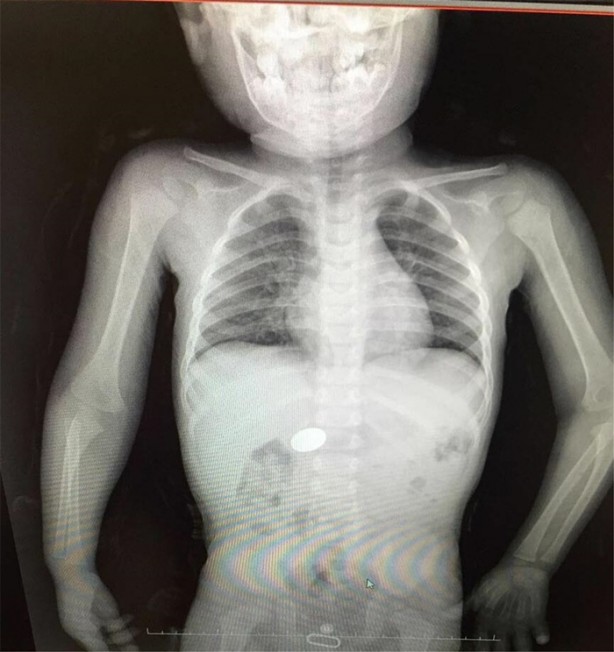

İzmir Tepecik Eğitim ve Araştırma Hastanesi Çocuk Gastroenteroloji Bölümü'nün, yabancı cisim yutan çocukların nefes ve borusu ile midelerinden çıkarttığı, anahtarlık, madeni para, saat pili, ataç, çengelli iğne ve çivi gibi objeler görenleri hayrete düşürdü.

Bu objelerden en tehlikelisinin piller olduğuna dikkat çeken Doç.Dr. Maşallah Baran, "Piller kimyasal mekanizmayla mukozayı yakıyor, özellikle yemek borusu çok duyarlı pillere, hele ki yeni takılmış bir pilse saatler içinde şahit olduğum bir kaç vaka var, yemek borusunu kömür haline getirebiliyor" dedi.